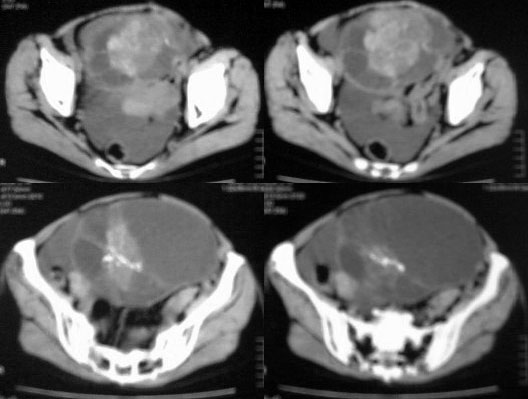

患者女性,45岁,因下腹疼痛,包块就诊,月经不太规则,其他未能提供有价值病史,请讨论

对不起各位,第一次试传,经验不足,补充一下资料,患者女性,45岁,因下腹疼痛,包块就诊,月经不太规则,其他未能提供有价值病史

卵巢囊腺癌伴腹膜转移可能性最大。

虽然没见到明显脂肪影,但是可见到明显钙化影,不排除恶性畸胎瘤的可能。

1.卵巢囊性畸胎瘤,2. 卵巢囊腺癌,道格拉斯腔积液。

ct图像有点不连续,且大部画面模糊,有增强吗?就此而论我看向源于卵巢的,首先考虑囊腺ca或瘤.

此患者手术病理结果已出:卵巢囊腺瘤。